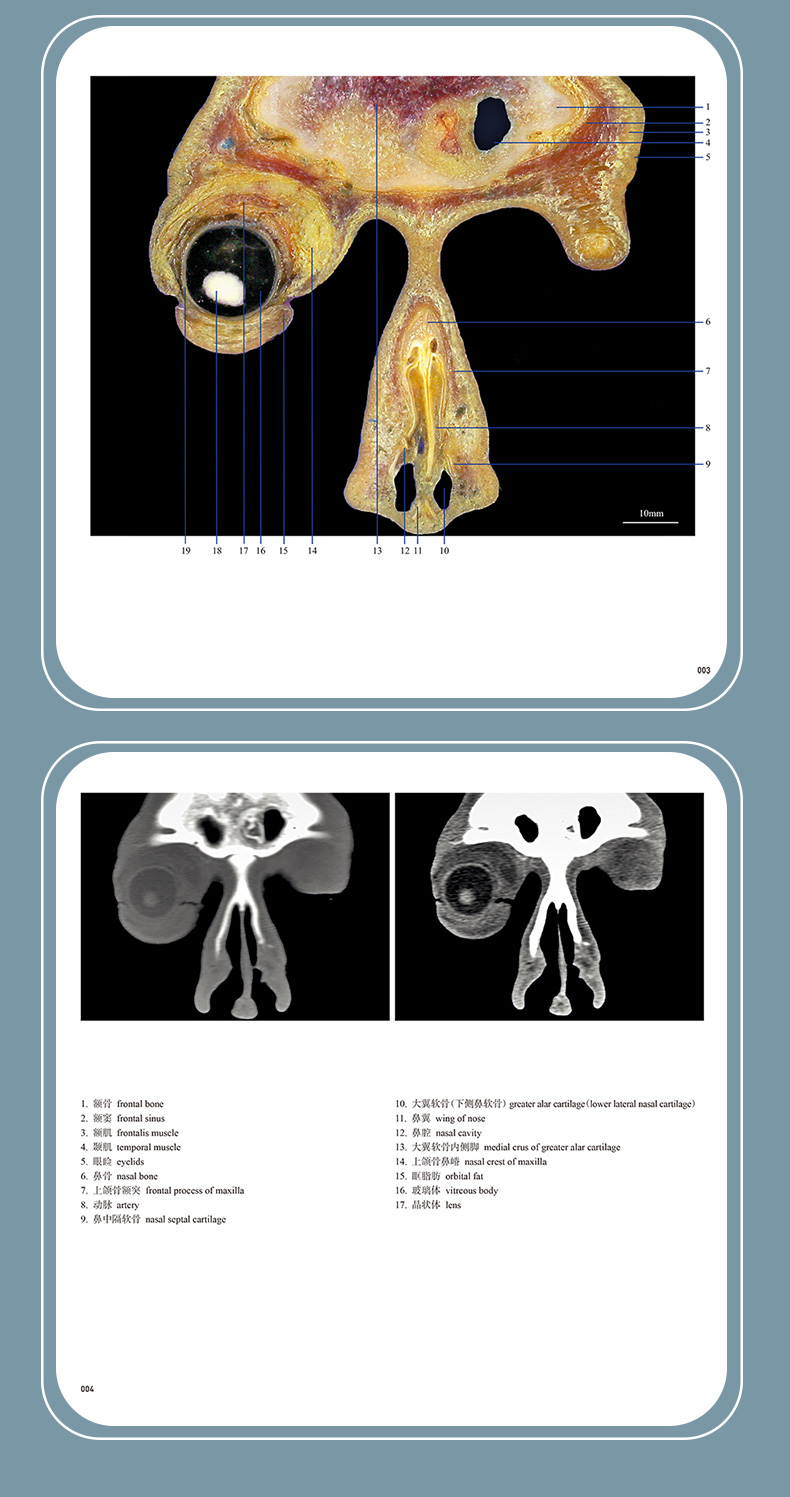

本书从数据集每隔1.2mm选取一幅图像,截取眼、耳、鼻及毗邻颅底的局部区域图像,共112幅图像。同时配以相应部位的CT图像对照。本书特色是断层解剖图利用数字图像处理技术优势,放大并清晰展示眼、耳、鼻及毗邻颅底断面的局部区域结构,组织色泽真实,甚至能够清晰显示肌肉纹理、筋膜纹路等细节结构,图像质量高于美国《人体断层解剖学彩色图谱》(引进版)类似图谱图像质量。对眼科、耳鼻咽喉科和神经内外科医生理解相关解剖结构有较大帮助。